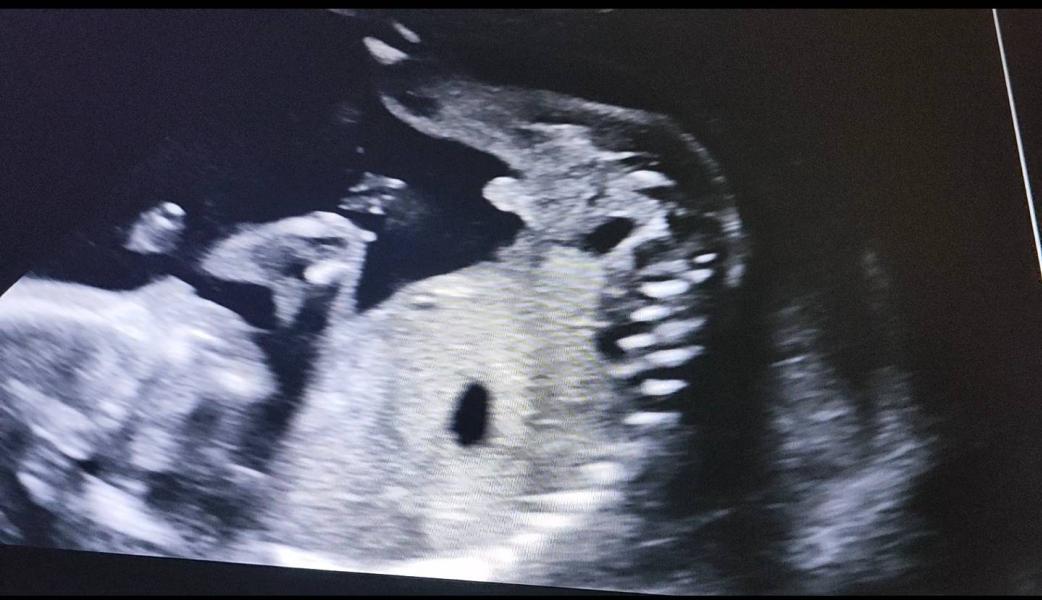

Вот это пиписька🫣 (извините) в первый раз такую богатырскую вижу)))

Слышала про косяки инвитро, но пошла туда потому что для моего села самые дешевые анализы у них, но пошла позже 12 недель чтобы наверняка. В день скрининга предположили девочку, а инвитро мальчика по крови насчитали, сегодня на узи были экспертном, мальчик уже во всей красе )))